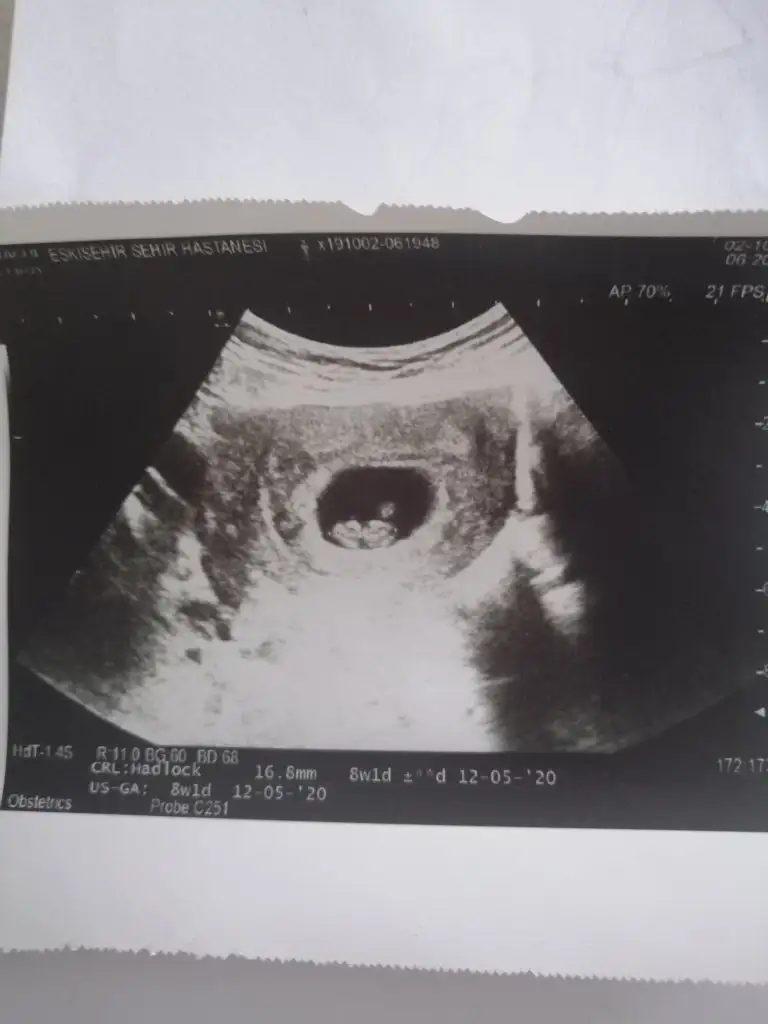

Evet nub dan baskasina cok inanmamak gerektigini vurguladim ben de:) diger teorileri cok kafaya takmis biri olarak.Nub teorisinde erkek yorumlamıştım usgnizi

vaginal ultrasonkizlar merhaba. simdi gordum boyle konu oldugunu. benim ilk bebegim, cinsiyeti onemli degil, saglikla ilerleyelim, saglikli dogsun, başka bir şey istemem. ama konuyu gordum, mezeye yazayim dedim. dogru sonuc versede vermesede, tahmin ede bilen varsa eyleniriz birazultrason 6haftalik

Kız gibi kesede neydi tahminKızlar daha önceydi keseyi atmıştımbirde böyle 12+5ten bir fotomuz var sizce tahminini nedir? 13+4 olduk öğrenemedim çok merak ediyorum